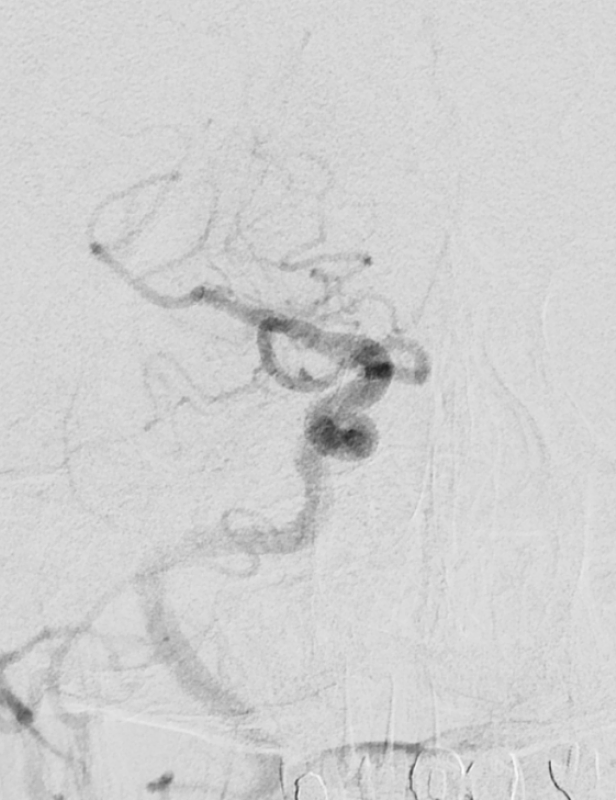

高鴻文主任舉例,一位五十二歲男性有高血壓病史病人,發病後滿分五分的力氣僅剩二分,在中大腦動脈血栓堵住情況下,經過取栓後讓血流順利通過,將大腦損傷降到最低。另一位病人是七十五歲伯伯,也是左邊中大腦動脈血栓堵住,到院時右側肢體僅剩二分力氣,口齒不清,病史包括糖尿病、高血壓、心臟病,經過取栓微創手術治療打通動脈後,讓大腦及時得到救援。

高鴻文主任說,從心臟到大腦的血栓,都可透過取栓微創手術得到救援,像另一位是患有多種慢性病的七十二歲婦人,到院時口齒不清,經檢查為內頸動脈堵住的血栓,即時透過取栓手術可讓大腦恢復血液供應,並提高病人治療後的改善程度。